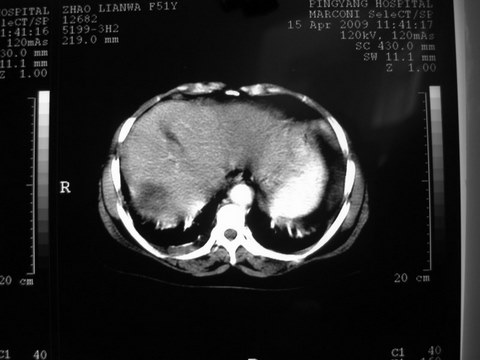

患者 女 51岁 两天前感觉上腹疼,无明显诱因,b超示肝右叶囊实性占位,边缘清楚,其内回声不均匀,ct增强如图,大家看看是什么 ,病人一年前及两月前b超检查只是提示胆囊炎

外院术后,证实肝癌合并出血

特点:1,病灶发展迅速,(2月前正常)[br] 2,囊实性,且并边界清晰光滑,呈右后叶赘生性。囊性区无强化,实性部分较多轻度强化,边界欠清。考虑囊腺癌或囊腺瘤。

出病理 中分化肝细胞癌合并出血